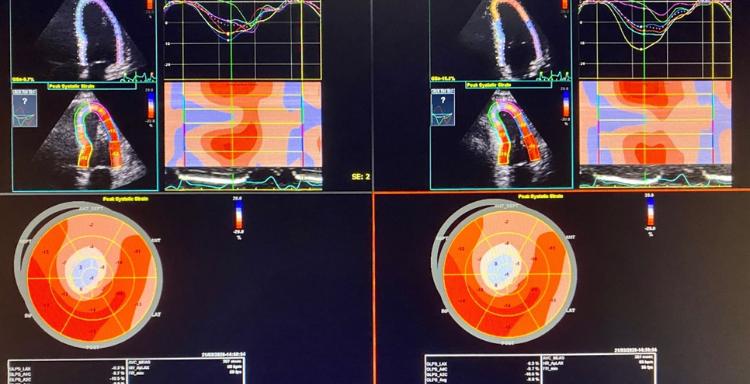

Η μυοκαρδιοπάθεια είναι ένα νόσημα του καρδιακού μυός. Δημιουργεί δυσκολία στην άντληση του αίματος από την καρδιά στο υπόλοιπο σώμα και μπορεί να δημιουργήσει συμπτώματα καρδιακής ανεπάρκειας. Οι μυοκαρδιοπάθειες συνδέονται επίσης και με αρρυθμίες όπως η κολπική μαρμαρυγή αλλά και κοιλιακή ταχυκαρδία ή κοιλιακή μαρμαρυγή. Άλλες επιπλοκές που εμφανίζονται είναι δυσλειτουργίες στις καρδιακές βαλβίδες ή θρομβοεμβολικά επεισόδια.

Υπάρχουν διάφορες μορφές μυοκαρδιοπαθειών. Οι πιο συνηθισμένες μυοκαρδιοπάθειες είναι η διατατική, η υπερτροφική και η περιοριστικού τύπου μυοκαρδιοπάθεια. Η αγωγή περιλαμβάνει φάρμακα, εμφύτευση ενδοκαρδιακών συσκευών όπως βηματοδότες ή απινιδωτές ή ακόμα και κατάλυση για τις αρρυθμίες που προκαλούνται. Σε τελικές μορφές μυοκαρδιοπαθειών μπορεί να χρειαστεί καρδιακή μεταμόσχευση.

Η αντιμετώπιση των μυοκαρδιοπαθειών απαιτεί ολιστική προσέγγιση με τη λήψη ατομικού και οικογενειακού ιστορικού, την κλινική εξέταση και με εργαστηριακές εξετάσεις οι οποίες μπορεί να περιλαμβάνουν γενετικό έλεγχο. Ακολουθεί η χορήγηση της κατάλληλης φαρμακευτικής αγωγής και η διαστρωμάτωση κινδύνου για καρδιακές αρρυθμίες. Οι καρδιακές αρρυθμίες μπορούν να αντιμετωπιστούν με φαρμακευτική αγωγή ή κατάλυση (ablation) αλλά σε μερικές περιπτώσεις κρίνεται σκόπιμη η εμφύτευση βηματοδότη ή απινιδωτή.